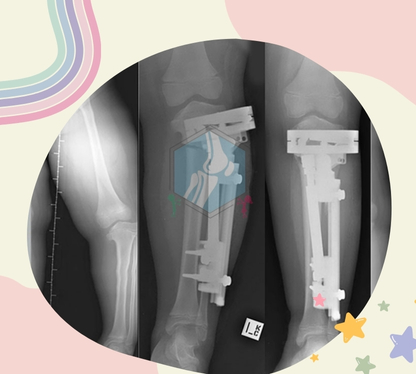

Best Treatment - If your child has clubfoot, it will make it harder to walk normally, so doctors generally recommend treating it soon after birth.…

Dr. Arpit Agrawal is a leading pediatric orthopedic surgeon in Indore, specializing in the diagnosis and treatment of birth deformities, clubfoot, and a wide range of pediatric orthopedic conditions. He has received extensive training from renowned institutions such as the Sancheti Institute, Pune, and Wadia Children’s Hospital, Mumbai. Further enhancing his expertise, Dr. Agrawal has gained international experience through advanced training and clinical work at National University Hospital (NUH), Singapore, along with exposure at various specialized centers in London. His comprehensive training and global experience enable him to deliver advanced, child-focused orthopedic care.